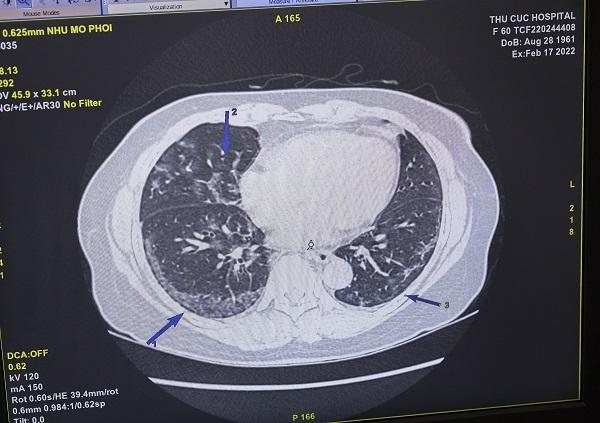

Một trường hợp khác là chị N.T.O đến Thu Cúc TCI khám với triệu chứng ho dữ dội và kéo dài. Chị O đã khỏi Covid-19 nhưng triệu chứng ho vẫn tiếp diễn và không có dấu hiệu thuyên giảm. Sau khi khám với bác sĩ nội khoa, chị được chỉ định làm xét nghiệm máu và chụp cắt lớp vi tính phổi. Hình ảnh trên phim chụp MSCT phổi của chị O cho thấy đã có tình trạng xơ phổi.

| Hình ảnh phổi của bệnh nhân O. bị tổn thương sau nhiễm virus Sars-CoV-2 (Ảnh: Thu Cúc TCI) |

Bác sĩ Nguyễn Quang Hanh chia sẻ, với những trường hợp nghi ngờ có tổn thương phổi sau nhiễm Covid-19 mà người bệnh có triệu chứng ho, thì cần thực hiện chụp cắt lớp vi tính phổi để chẩn đoán tổn thương. Bởi nếu chụp X-quang sẽ không nhìn thấy hoặc rất khó đánh giá chính xác. Hiện nay, Thu Cúc TCI đang áp dụng chụp cắt lớp vi tính giảm liều, giúp giảm tối đa bức xạ cho người bệnh mà vẫn đảm bảo kết quả chụp được rõ nét và chính xác.

Với tình trạng trên của chị O, bác sĩ điều trị sẽ lên phác đồ để phục hồi dần các nhu mô phổi bị tổn thương, giúp chị ổn định lại sức khỏe.